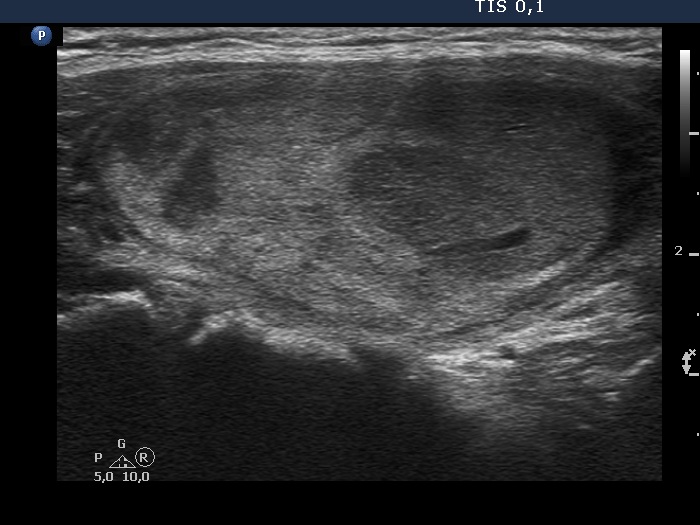

Ultrasonography. The thyroid was echonormal. There was a heterogeneous nodule in the right lobe. The lesion contained roughly equal proportions of echonormal and moderately hypoechoic portions. The nodule had a thin halo and presented perinodular blood flow.